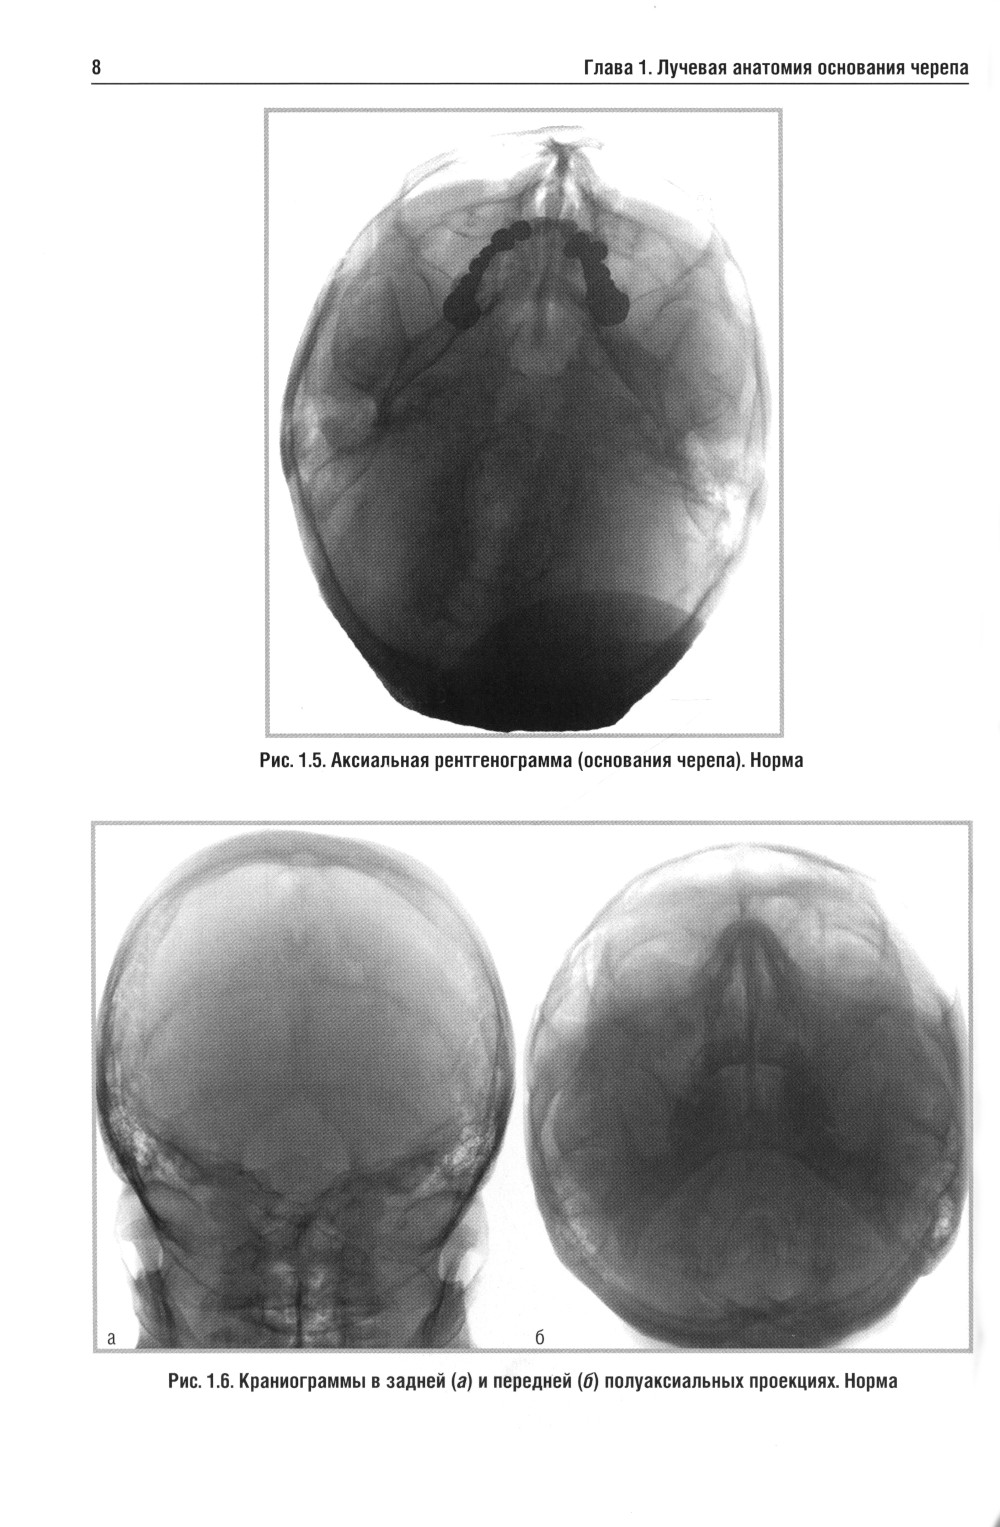

В учебном пособии изложена нормальная лучевая анатомия основания черепа по данным рентгенологического исследования, КТ и МРТ. Вторая и третья главы посвящены описанию лучевой семиотики наиболее часто встречающихся заболеваний основания черепа и мостомозжечкового угла, в которых представлены данные рентгенологического исследования, КТ и МРТ. Даются рекомендации по тактике лучевого исследования, приводится дифференциальная диагностика. Рассматриваются вопросы этиологии, патогенеза, морфологии и клинические проявления заболеваний. Для врачей, обучающихся по лучевой диагностике, нейрохирургии и неврологии. Пособие может быть рекомендовано для подготовки в системе последипломного профессионального образования.| Издательство | Элби |